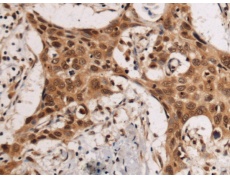

IHC positive control: |

Human esophagus cancer |